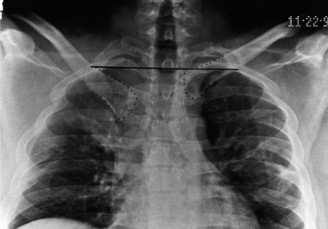

A PA view of the chest is the only radiograph available. What additional view would be most beneficial?

Discussion

The correct answer is (D). A serendipity view is a 40-degree cephalic-tilt view (Fig. 2–70). This provides a true caudocephalic view of both the SC joint and the medial clavicles. The serendipity view is usually the front line radiograph obtained, however, computed tomography (CT) is the best technique to study the SC joint. Other radiographic views of the SC joint include the Heinig view and the Hobbs view. The lateral view of the chest cannot be used to interpret SC joint dislocations because of the overlap of the medial clavicles with the first rib and the sternum. A swimmer’s view is used for increased visualization of the subaxial cervical spine. The stryker notch view is used for evaluating Hill-Sachs lesions of the humeral

Figure 2–70